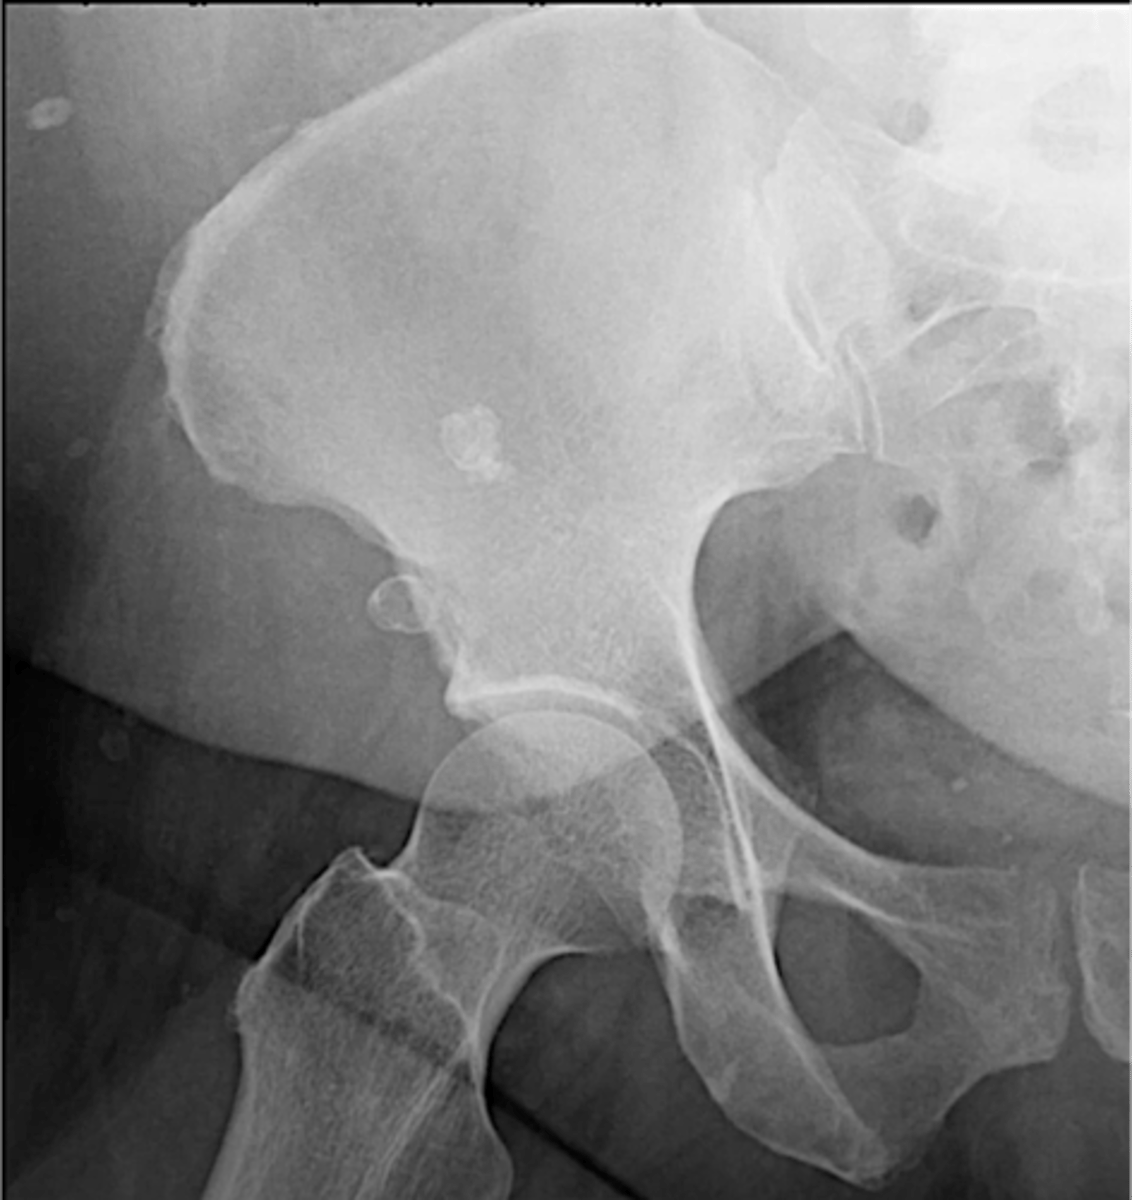

Aortic aneurysm calcification

Abdominal aortic aneurysm calcification

Abdominal aortic aneurysm calcification (pic 2)

Abdominal aortic aneurysm calcification (pic 3)